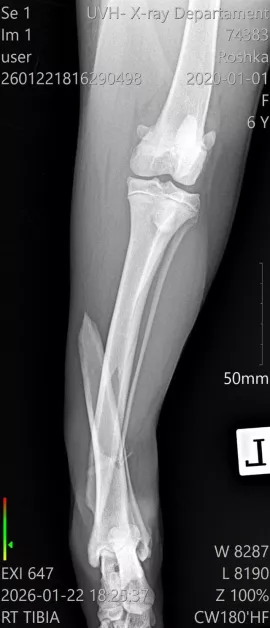

Диагнозата е тежка – две съществени фрактури на задните крака в региона на пищялите, с разбъркване и травмирани меки тъкани. По думите на ортопеда съществува действителен късмет фрактурите да бъдат закрепени с импланти и винтове, което би разрешило на Рошка още веднъж да проходи.